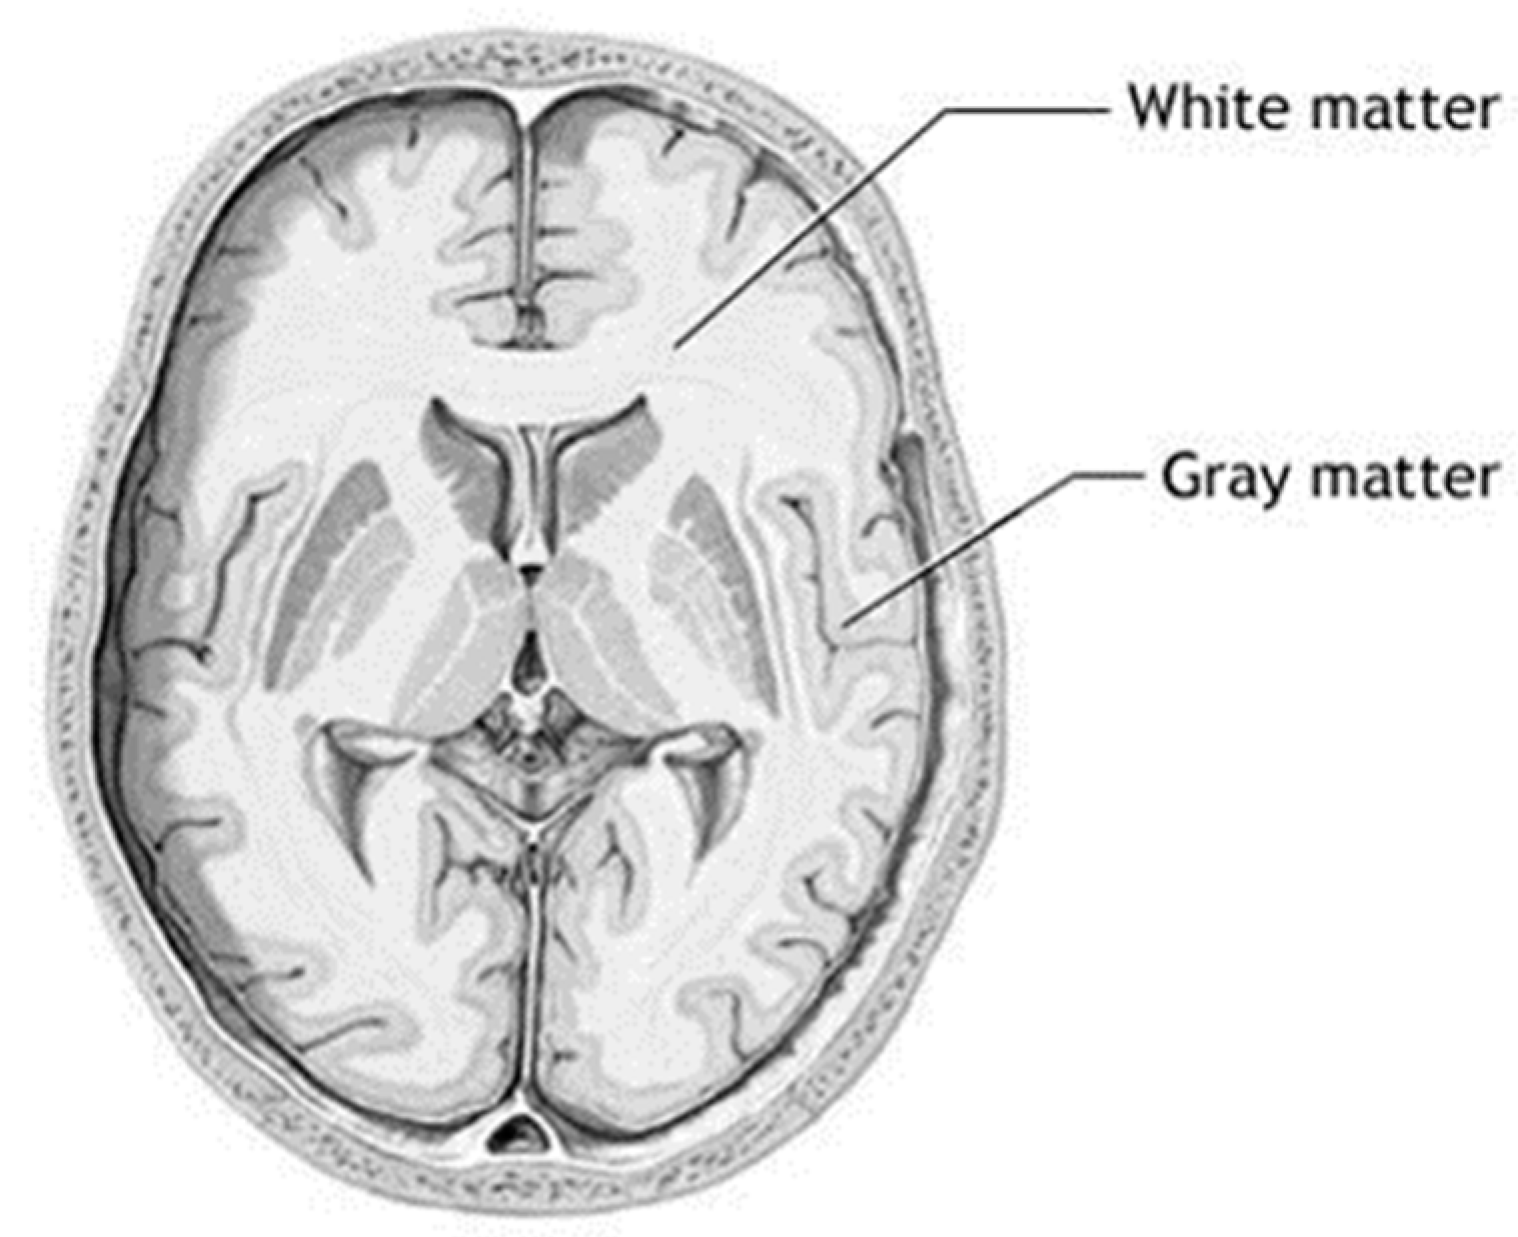

3.1. Step 1 Preprocessing Phase